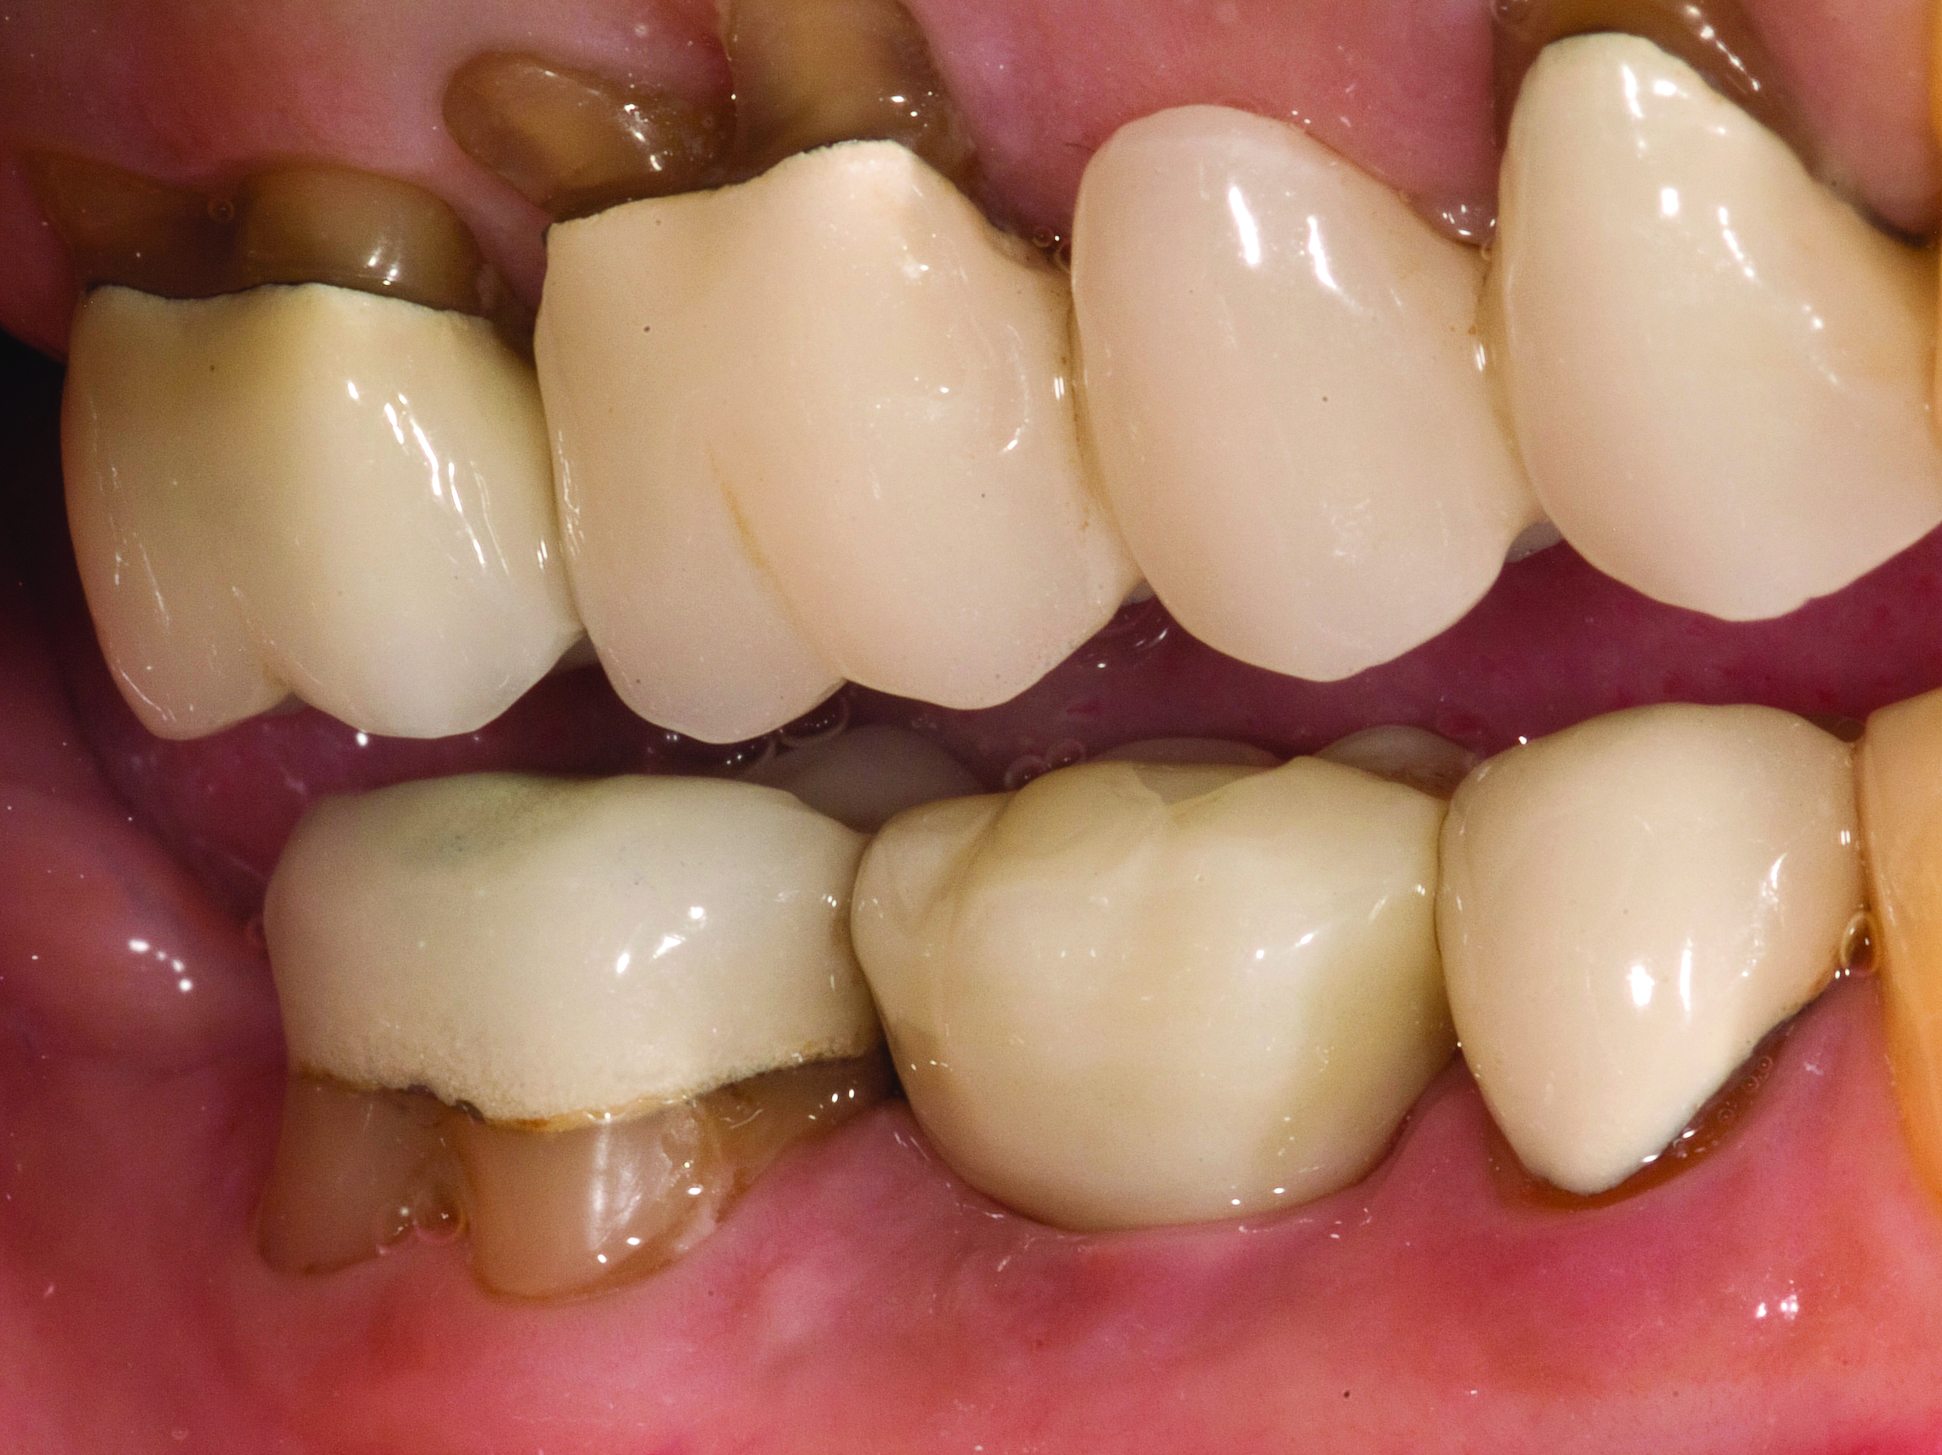

Case Presentation

A mandibular right first molar was extracted due to an advanced Class III furcation and an irreversible pulpitis—a combination lesion. An immediate implant placement protocol was elected, and a PEEK abutment was placed on the implant (Figure 1). After 3 months of healing, a scan body was placed on the osseointegrated implant (Figure 2 and Figure 3), and an intraoral scan was taken (TRIOS Pod) (Figure 4) for the fabrication of a screw-retained crown.

Once the STL file generated from the intraoral scanner was sent to the laboratory (Figure 5), the technician used proprietary software to design the crown (Figure 6 through Figure 8), mill the crown, and digitally print a SLA model (Dental SG, Formlabs, www.formlabs.com) (Figure 9 through Figure 11), and then finish the crown on the digitally printed model. The angulated screw-channel full-zirconia crown (Nobel Biocare) (Figure 12) was seated, and contacts were evaluated intraorally and adjusted extraorally. The screw-retained crown was torqued to 35 Ncm2, and the screw access was sealed (Figure 13 through Figure 15).

Fig 3. Confirmation of seating of scan body.

Figure 3

Fig 14. Screw-retained implant crown replacing missing first molar, buccal view.

Figure 14

Fig 15. Final restoration of mandibular right first molar.

Figure 15